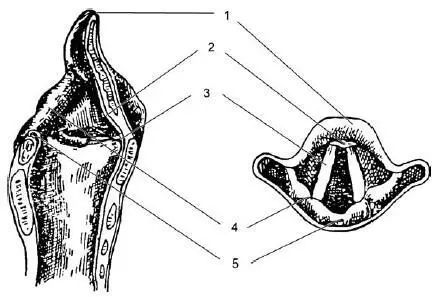

Рис. 19.3.Проекции различных анатомических образований гортани на видимое их изображение при непрямой ларингоскопии:

1 – край надгортанника; 2 – бугорок надгортанника; 3 – голосовая складка; 4 – черпаловидный хрящ; 5 —межчерпаловидное пространство